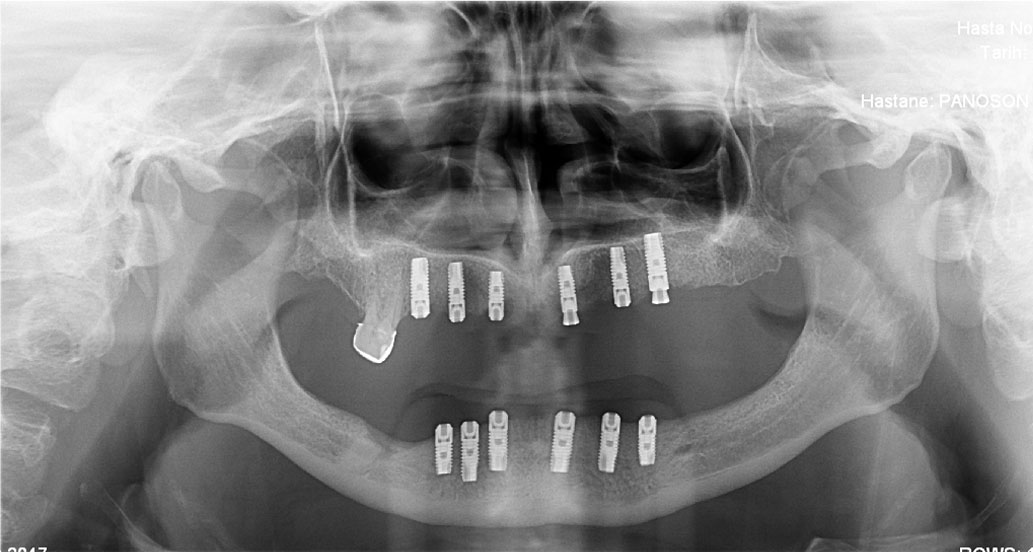

İmplant (Diş kökü olmayan bölgelere uygulanan suni kökler)